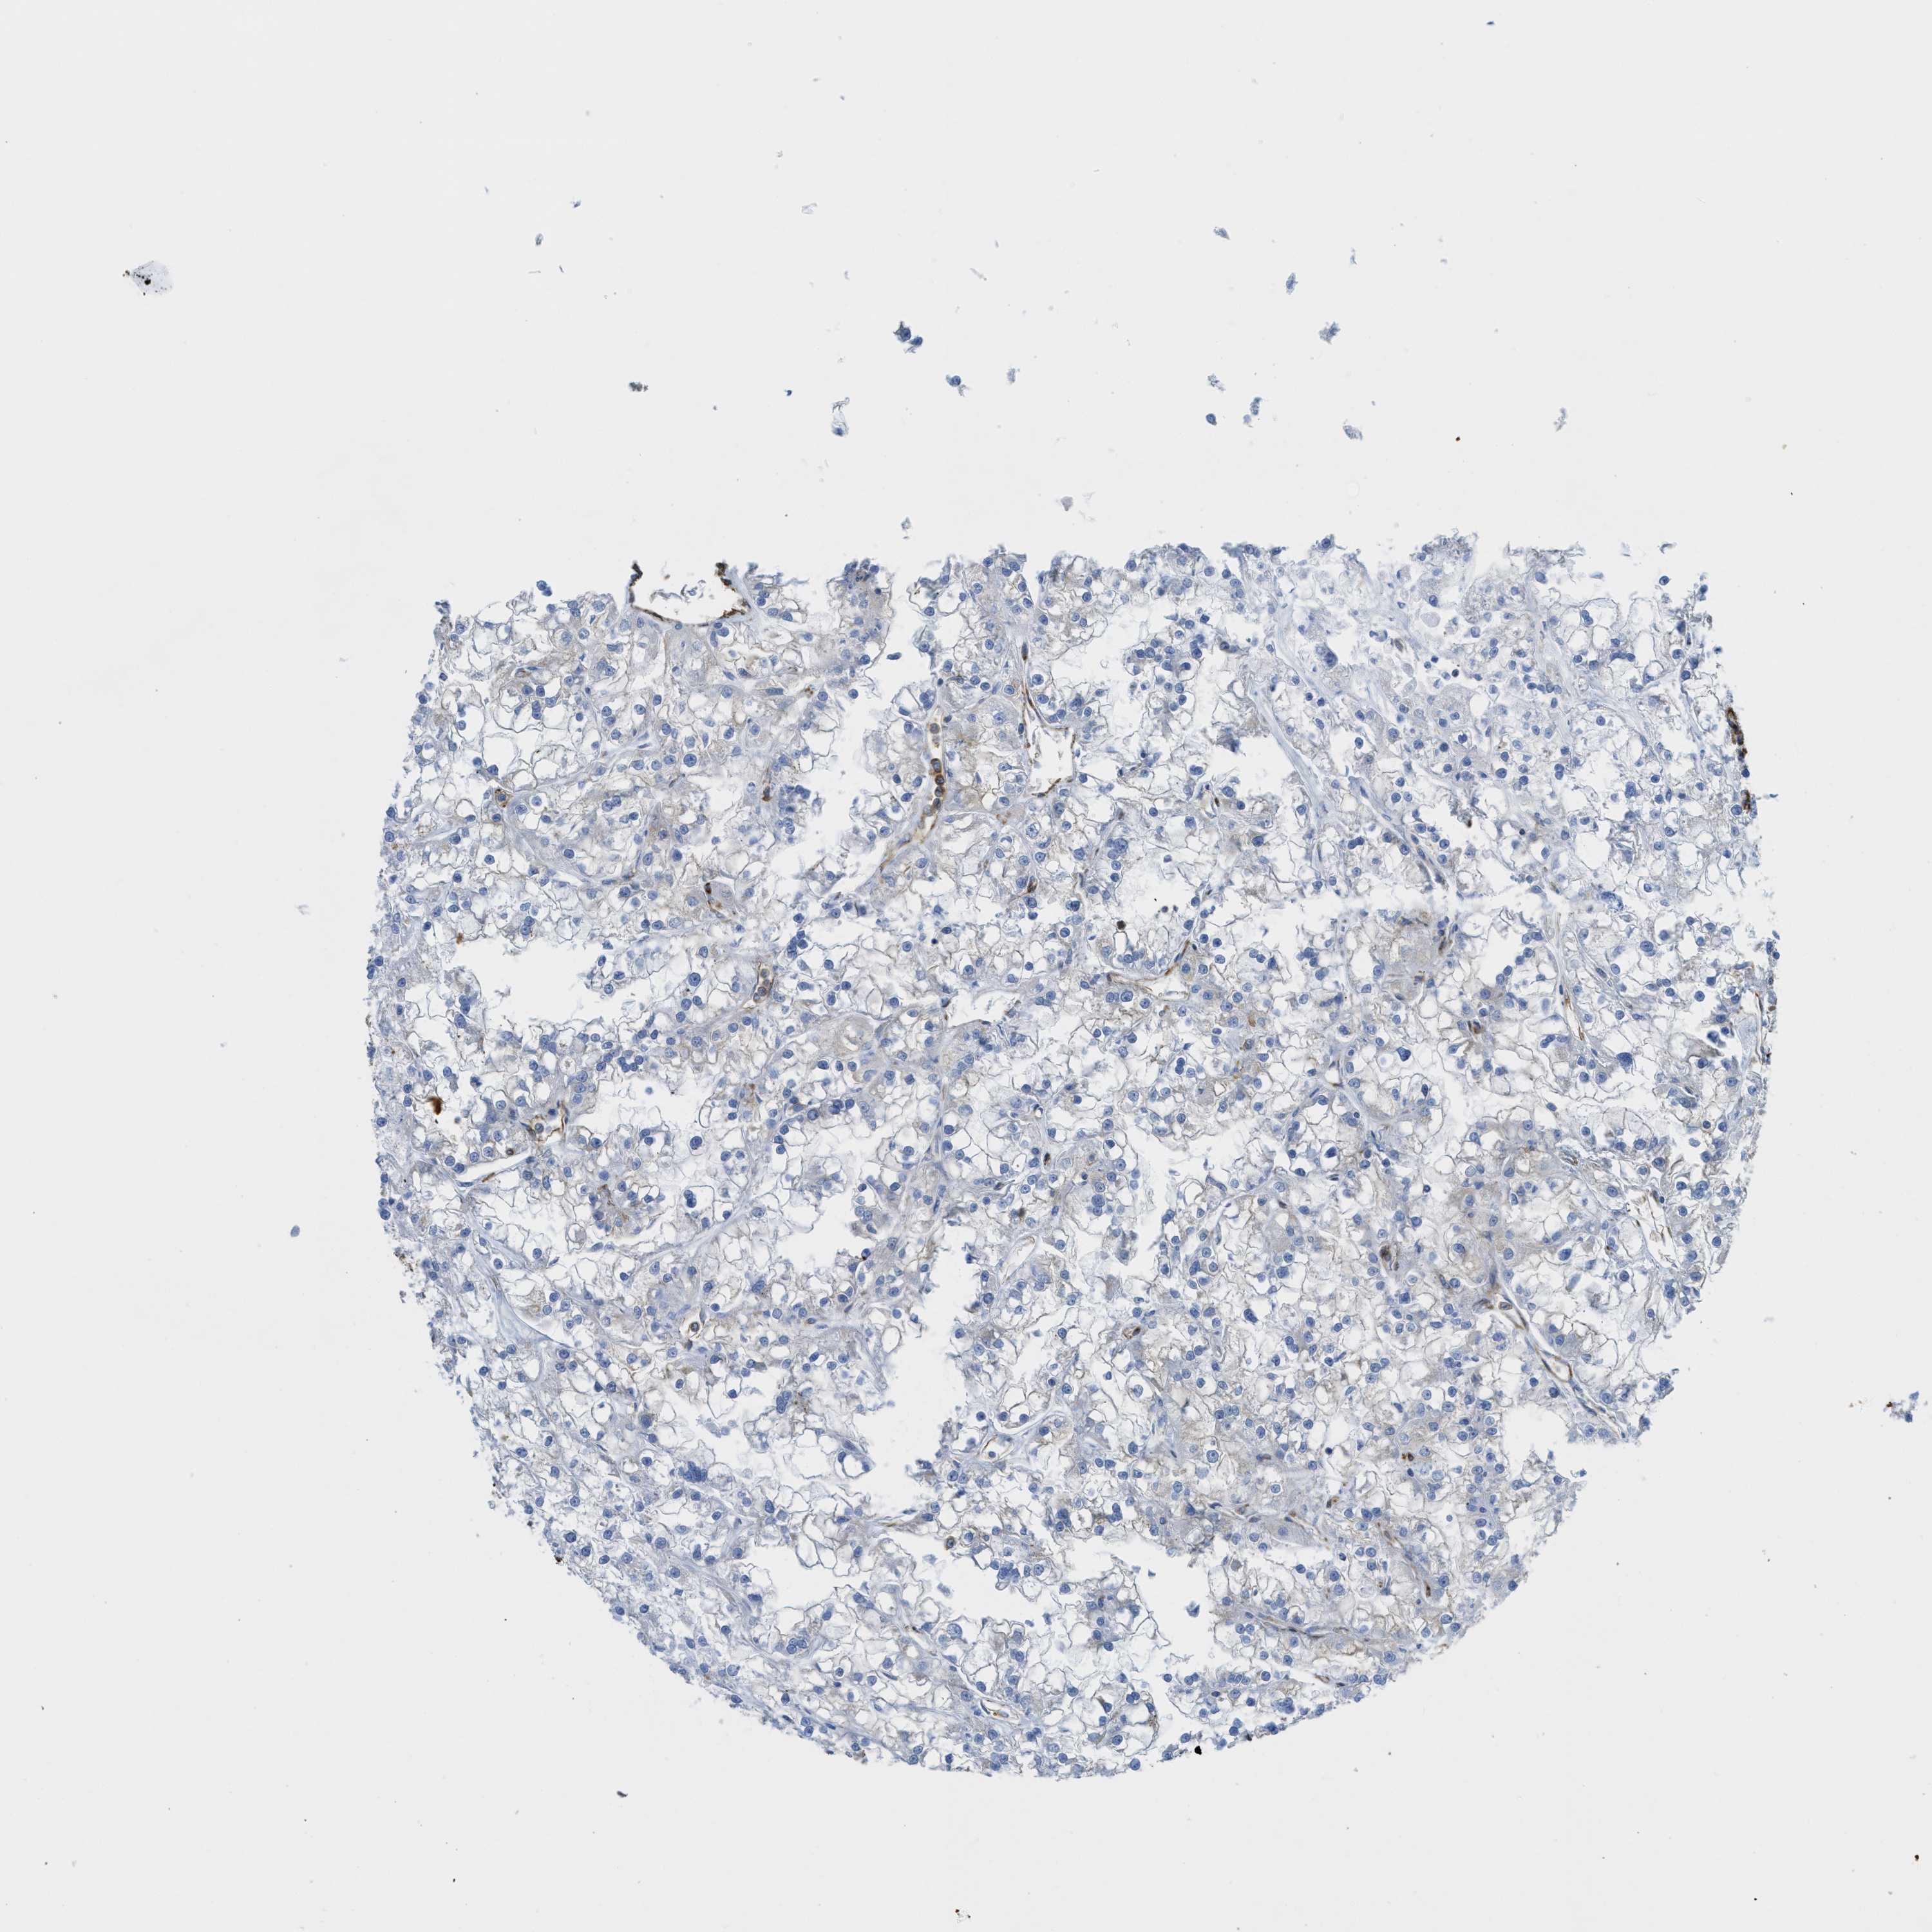

KIDNEY RENAL PAPILLARY CELL CARCINOMA (TCGA) - Interactive survival scatter ploti

The Survival Scatter plot shows the clinical status (i.e. dead or alive) for all individuals in the patient cohort, based on the same data that underlies the corresponding Kaplan-Meier plots. Patients that are alive at last time for follow-up are shown in blue and patients who have died during the study are shown in red.

The x-axis shows the expression levels (FPKM) of the investigated gene in the tumor tissue at the time of diagnosis. The y-axis shows the follow-up time after diagnosis (years). Both axes are complimented with kernel density curves demonstrating the data density over the axes. The top density plot shows the expression levels (FPKM) distribution among dead (red) and alive patients (blue). The right density plot shows the data density of the survived years of dead patients with high and low expression levels respectively, stratified using the cutoff indicated by the vertical dashed line through the Survival Scatter plot. This cutoff is automatically defined based on the FPKM cutoff that minimizes the p-score. The cutoff can be changed by dragging the vertical line or by entering a cutoff value in the square labeled "Current cut-off".

Under the Survival Scatter plot the p-score landscape (black curve; left axis) is shown together with dead median separation (red curve; right axis). Dead median separation is the difference in median mRNA expression between patients who have died with high and low expression, respectively. It is calculated as follows: median FPKM expression of dead patients with high expression - median FPKM expression of dead patients with low expression. This is intended to aid the user in visually exploring custom cutoffs and the associated p-scores and dead median separation.

Individual patient data is displayed and can be filtered by clicking on one or more of the category buttons on the top of the page. Categories describing expression level and patient information include: high, low, alive, dead, female, male and tumor stages. The scale of the x-axis can be toggled between linear and log-scale by clicking on the "x log" button. Mouse-over function shows TCGA ID, patient information and mRNA expression (FPKM) for each patient.

& Survival analysisi

Kaplan-Meier plots summarize results from analysis of correlation between mRNA expression level and patient survival. Patients were divided based on level of expression into one of the two groups "low" (under cut off) or "high" (over cut off). X-axis shows time for survival (years) and y-axis shows the probability of survival, where 1.0 corresponds to 100 percent.

HIP1 is not prognostic in Kidney Renal Papillary Cell Carcinoma (TCGA)